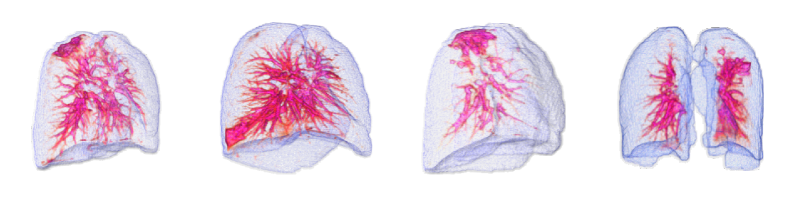

By using the internal clinical dataset from SMC of pneumonia and tuberculosis cases, we experimentally verified the superiority of the proposed VMPR-UAD through various comparative experiments. We also provide quantitative results and 3D abnormal (lesion) localization/visualization results of VMPR-UAD using the internal dataset for pneumonia and tuberculosis in the Supplementary Material to illustrate the superiority of anomaly localization by VMPR-UAD.

Finally, we evaluated the 3D abnormal (lesion) localization performance of the proposed VMPR-UAD. Of the 63 cancer cases in the MSD dataset with ground-truth annotations available, we excluded two cases (cases 38 and 96) of incorrect annotation or showing other diseases. We calculated whether the cancer area predicted by VMPR-UAD (binarized at a certain high-probability threshold) overlapped with the annotated cancer area. As a result, 57 of the 61 cases showed overlapping, demonstrating that VMPR-UAD can localize 3D lung anomalies (cancer in this case) with an accuracy of 93. Some localization examples in 3D data are shown in Fig. L. The red points in Fig. L(b) show the 3D cancer locations that the proposed method estimates with the highest confidence (i.e., location of highest pixel value in the 3D anomaly map). The red points in Fig. L(a) show the ground-truth cancer location. The ground truth and prediction shown in Fig. L confirm that VMPR-UAD correctly finds the lung anomaly 3D region. More detailed visualization results are available in the Supplementary Material. The prediction consistency can also be observed in 2D slices, as shown in Fig. M, where our anomaly localization map indicates correct cancer regions. Hence, the proposed VMPR-UAD can automatically localize or segment lesions without requiring any lesion information (i.e., using only CT slices from healthy subjects) for training.